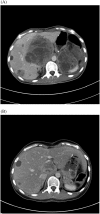

Follicular dendritic cell sarcoma (FDCS) is a very rare malignant tumor derived from follicular dendritic cells. Radical resection is the standard therapy for patients with local disease, but an optimal chemotherapy regimen has not been determined for unresectable disease. We report our experience of an FDCS patient with multiorgan involvement. In the present case, disease was only located in the pancreas initially and radical resection was performed. Multiple metastasis developed after the treatment and several factors that indicated a poor prognosis were observed. The present case had a very poor prognostic disease but survived for a long time with a good performance status because of the multiple chemotherapy regimens, which follow therapeutic strategies for malignant lymphoma and soft tissue sarcoma. As far as we know, this is the first study reporting the indication of bendamustine for FDCS patients.